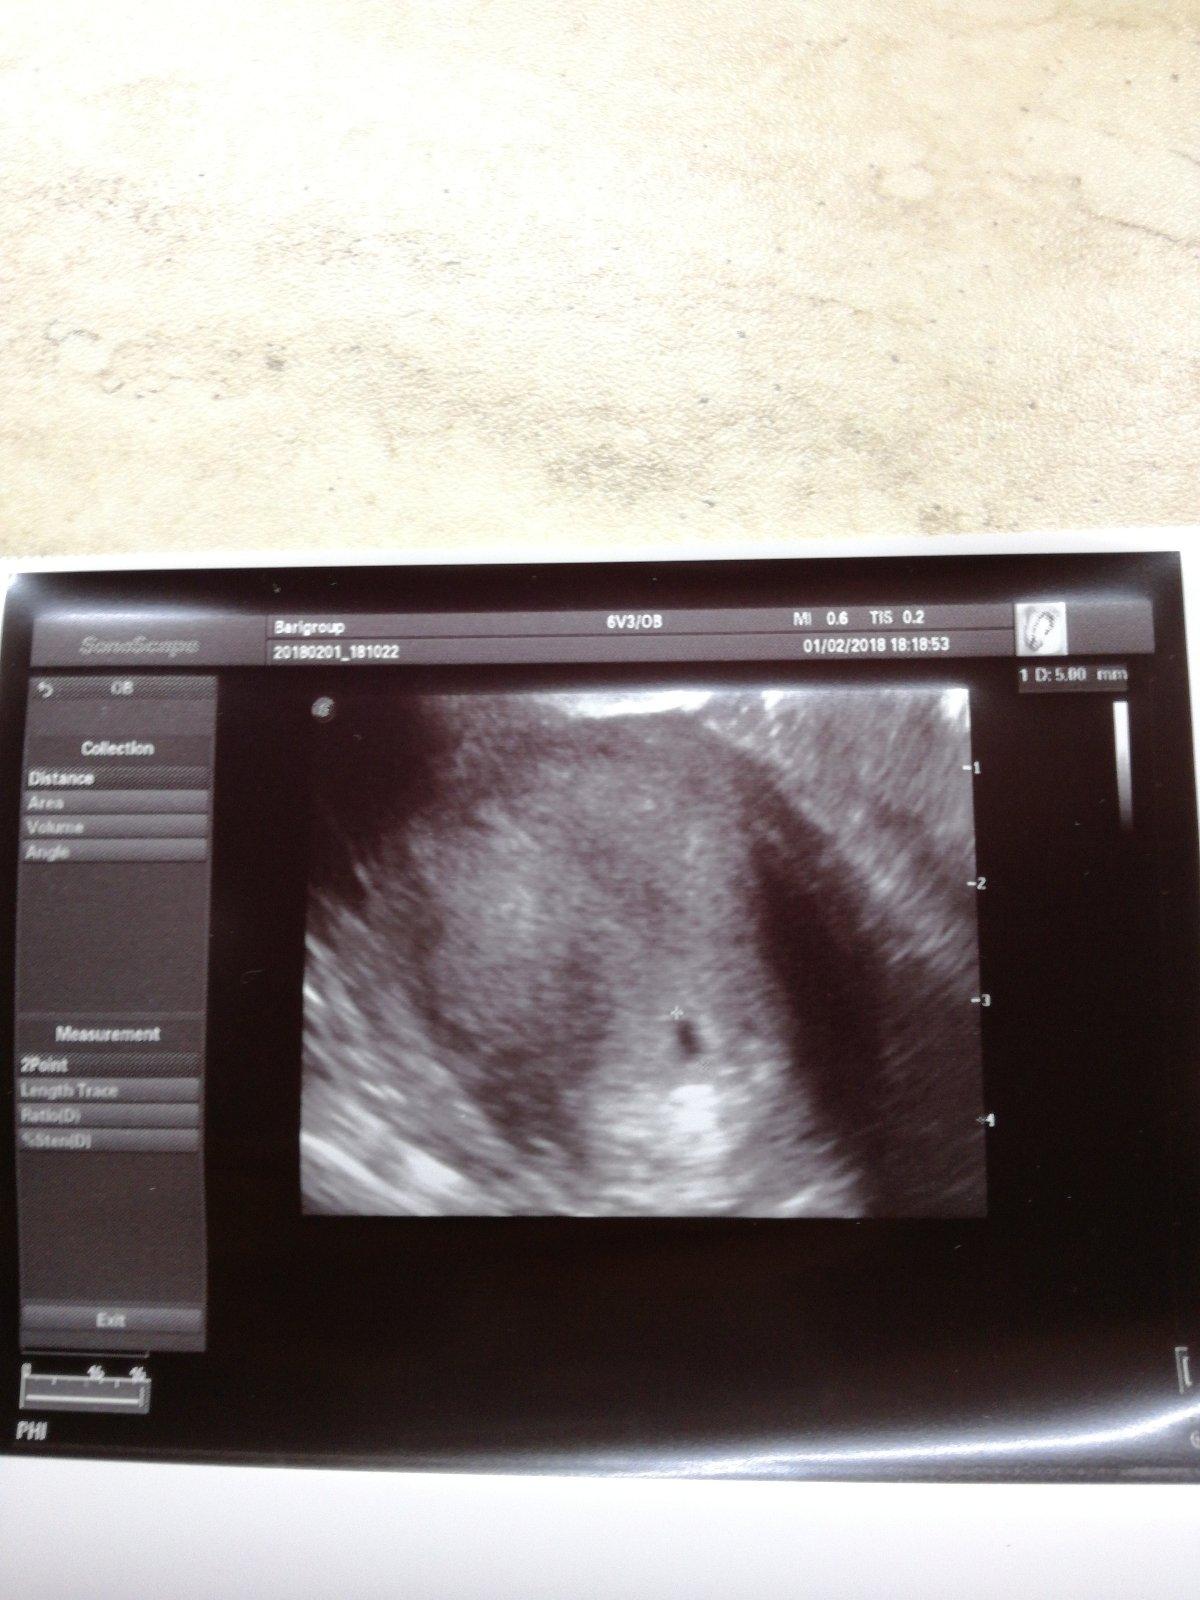

@tonjadabik2 o fotke z UZV na predchádzajúcej strane, ktorú sewie zverejnila. Len som ju chcela upozorniť, že tam má rodné číslo a to sa nezverejňuje. To je celé. Nič iné tým myslené nebolo.